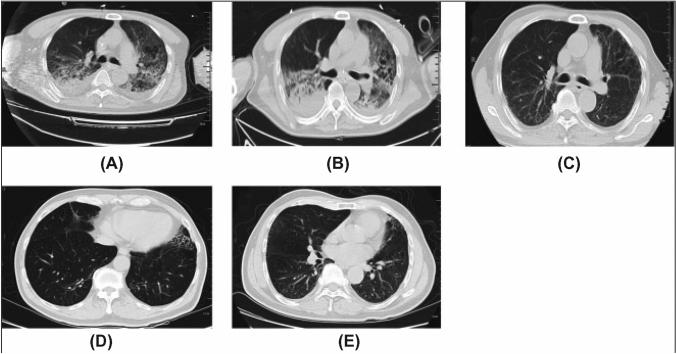

COVID-19 has severely devastated many lives across the globe. It has been speculated that stem cell-based therapy for COVID-19 treatment could be able to subsidize the effects. In preclinical and clinical studies, stem cell-based therapy has successfully eliminated inflammatory cytokines in ALI, ARDS, and COVID-19. Clinical trials have produced a variety of promising results for validating stem cell therapy in COVID-19 patients. For instance, exosome-based therapy (ExoFlow) showed an 87% survival status, and MSC-based therapy (Mesoblast) achieved an 83% survival rate in moderate to severe COVID-19 patients. This review debates the advantages of cell-free therapy, i.e., stem cell-derived exosome-based therapies, over stem cell-based therapy. This review aims to question whether the immunomodulatory effect of stem cells differs based on their origin and also tries to find possible answers for the best stem cells for treating SARS-CoV-2 infection. The role of stem cells and their extracellular vesicles in the upregulation of regulatory immune cells, growth factors (EGF, FGF, VEGF), and anti-inflammatory cytokines (IL-6, INF-α, galectin-1, notch-1, PDL-1) that promote the tissue regeneration at the injured site. The right side of the image depicts the downregulation of inflammation-inducing immune cells, pro-inflammatory cytokines, and chemokines that could also enhance COVID-19 therapy.

新型冠状病毒肺炎(COVID-19)在全球范围内严重影响了许多人的生活。有人推测,基于干细胞的治疗方法可能有助于缓解 COVID-19 的影响。在临床前和临床研究中,基于干细胞的治疗方法已成功消除了急性肺损伤(ALI)、急性呼吸窘迫综合征(ARDS)和 COVID-19 中的炎症细胞因子。临床试验为验证 COVID-19 患者的干细胞治疗提供了多种有前途的结果。例如,基于外泌体的治疗(ExoFlow)显示出 87%的存活状态,基于间充质干细胞的治疗(Mesoblast)在中度至重度 COVID-19 患者中达到 83%的存活率。本综述讨论了无细胞治疗(即基于干细胞衍生的外泌体治疗)优于基于干细胞的治疗的优势。本综述旨在质疑干细胞的免疫调节作用是否因其起源而异,并尝试为治疗 SARS-CoV-2 感染的最佳干细胞寻找可能的答案。干细胞及其细胞外囊泡在调节性免疫细胞、生长因子(EGF、FGF、VEGF)和抗炎细胞因子(IL-6、INF-α、半乳糖凝集素-1、 Notch-1、PDL-1)的上调中的作用,这些因子促进受损部位的组织再生。图像的右侧描述了炎症诱导免疫细胞、促炎细胞因子和趋化因子的下调,这也可能增强 COVID-19 的治疗效果。